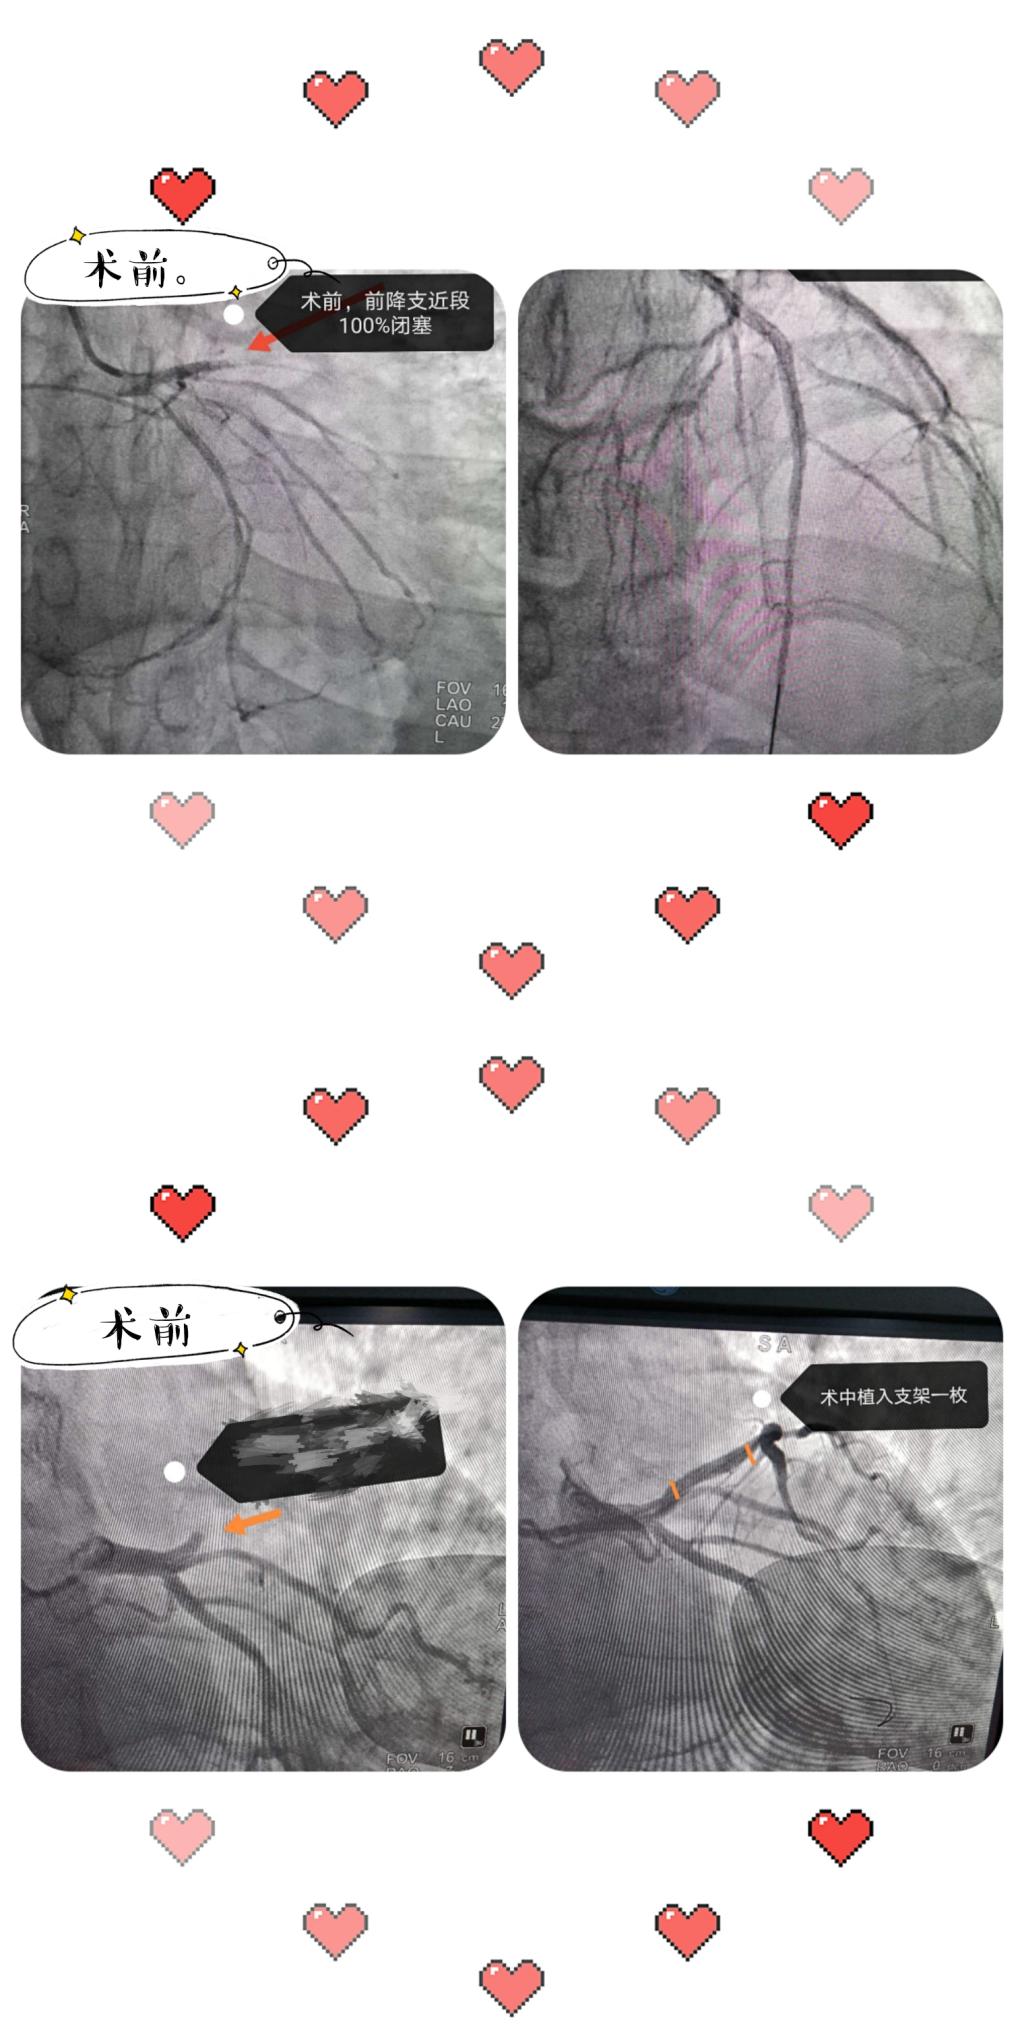

曾经上班,遇到一个34岁男性患者,胸闷不适来诊,于急诊科急查心电图为急性心肌梗死,立即给予请心血管内科医师会诊并开通胸痛绿色通道,迅速完善相关检查,急诊手术。最终患者得到了快速且有效的治疗。由此可见,疾病正在年轻化。今年至今我院急诊科已接诊胸痛心梗患者已过百余人。可能很多人问:为什么现在生活条件好了,疾病却越来越年轻化呢?这俺也不知道。

心肌梗死,字面意思就是心脏肌肉梗死,就是说某个东西把心脏血管这条路堵死了;专业一点就是在冠状动脉粥样硬化狭窄基础上,由于某些诱因致使冠状动脉粥样斑块破裂,血中的血小板在破裂的斑块表面聚集,形成血块(血栓),突然阻塞冠状动脉管腔,导致心肌缺血坏死。

西安凤城医院于2018年建立胸痛急救绿色通道。自建立胸痛急救绿色通道以来,使急性心肌梗死患者能在短时间内开通堵塞的血管,挽救了心脏的“路”也挽留了生命。